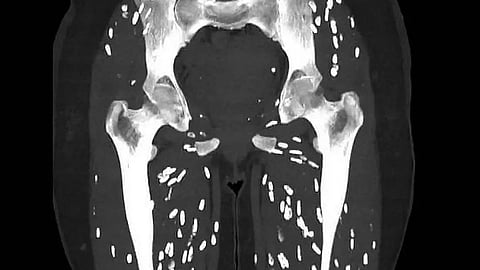

വേവിക്കാത്ത പന്നിയിറച്ചി കഴിച്ചതിന് പിന്നാലെ ​ഗുരുതര പാരസൈറ്റ് ഇൻഫെക്ഷൻ ബാധിച്ച രോ​ഗിയുടെ സിടി സ്കാൻ പങ്കുവെച്ച് ഡോക്ടർ. കാലുകളിൽ ​ഗുരുതരമായി ഇൻഫെക്ഷൻ വ്യാപിച്ചത്തിന്റെ ഞെട്ടിക്കുന്ന ചിത്രമാണ് ഫ്ലോറി‍ഡ‍ എമർജൻസി ഡിപ്പാർട്മെന്റിലെ ഫിസിഷൻ ഡോ. സാം ​ഗാലിയാണ് എക്സിലൂടെ പങ്കുവെച്ചത്.

ഇതുവരെ കണ്ടെതിൽ വെച്ച് ഏറ്റവും ഭീകരമായ സിടി സ്കാൻ, ഇത് എന്ത് രോ​ഗമാണെന്ന് മനസിലായോ എന്ന അടിക്കുറുപ്പോടെയാണ് ഡോക്ടർ ചിത്രം പങ്കുവെച്ചിരിക്കുന്നത്. സിസ്റ്റിസിർകോസിസ് എന്ന പാരസൈറ്റ് ഇൻഫെക്ഷനാണ് ഇതെന്നും പിന്നീട് ഡോക്ടർ കമന്റിൽ വ്യക്തമാക്കുന്നുണ്ട്. ടീനിയ സോലിയം എന്ന നാടവിരയുടെ മുട്ടയിൽ നിന്നാണ് ഈ അണുബാധ ഉണ്ടാകുന്നത്. പന്നികളിൽ കാണപ്പെടുന്ന നാടവിരയിലെ ലാർവൽ സിസ്റ്റുകൾ ഇറച്ചി നന്നായി വേവിക്കാത്തതു മൂലം ശരീരത്തിൽ എത്തുകയും. അണുബാധയ്ക്ക് കാരണമാവുകയും ചെയ്യുന്നു.

അഞ്ചു മുതൽ പന്ത്രണ്ട് ആഴ്ചകൾക്കുള്ളിൽ ശരീരത്തിലെ ദഹനനാളത്തിൽ വച്ചുതന്നെ പൂർണ വളർച്ചയെത്തിയ നാടവിരകളായി ഇവ മാറുന്നു. തുടർന്ന് ഇവ മുട്ടകൾ ഉൽപ്പാദിക്കുന്നു. ഈ ലാർവകൾ കുടൽഭിത്തിയിൽ തുളച്ചുകയറി രക്തപ്രവാഹത്തിലേക്കും ശരീരത്തിന്റെ മറ്റുഭാ​ഗത്തിലേക്കും വ്യാപിക്കുന്നു. ഭക്ഷണത്തിലൂടെയാണ് ടീനിയ സോലിയം മനുഷ്യശരീരത്തിലെത്തുക.

ഈ ലാർവകൾ മസ്തിഷ്കത്തിലെത്തി സിസ്റ്റുകൾ രൂപപ്പെടുമ്പോൾ ന്യൂറോസിസ്റ്റിസിർകോസിസ് എന്ന അവസ്ഥയാകുന്നു. തലവേദന, ശ്രദ്ധക്കുറവു, ആശയക്കുഴപ്പം, ചുഴലി തുടങ്ങി പലവിധ നാഡീസംബന്ധമായ രോ​ഗങ്ങൾക്കും ഇത് കാരണമാകാം. പലപ്പോഴും സിസ്റ്റിസിർകോസിസിന്റെ രോ​ഗസ്ഥിരീകരണം വൈകുന്നതാണ് പ്രധാനവെല്ലുവിളിയെന്നും ഡോ. സാം കുറിക്കുന്നു. ഗുരുതരാവസ്ഥയിലെത്തിയതിനു ശേഷമാകും പലരും ചികിത്സ തേടുക.

ഇത്തരം അണുബാധ ഉണ്ടാകാതിരിക്കാൻ പരമാവധി ശുചിത്വം പാലിക്കുക, കൈകൾ വൃത്തിയായി കഴുകുക, വേവിക്കാത്ത പന്നിയിറച്ചി കഴിക്കാതിരിക്കുക എന്നിവ ശ്രദ്ധിക്കണമെന്നും അദ്ദേഹം കുറിക്കുന്നു. ഓരോവർഷവും അമ്പതുദശലക്ഷം പേർ ഈ അണുബാധയ്ക്ക് ഇരകളാകുന്നുണ്ടെന്നും അതിൽ 50,000 പേർ മരണപ്പെടുന്നുണ്ടെന്നും ഡോ. സാം കുറിച്ചു. ആന്റി പാരസൈറ്റിക് തെറാപ്പി, സ്റ്റിറോയ്ഡുകൾ, ആന്റി എപിലെപ്റ്റിക്സ്, ശസ്ത്രക്രിയയിലൂടെയുള്ള നീക്കംചെയ്യൽ തുടങ്ങിയവയാണ് പ്രധാന ചികിത്സ.